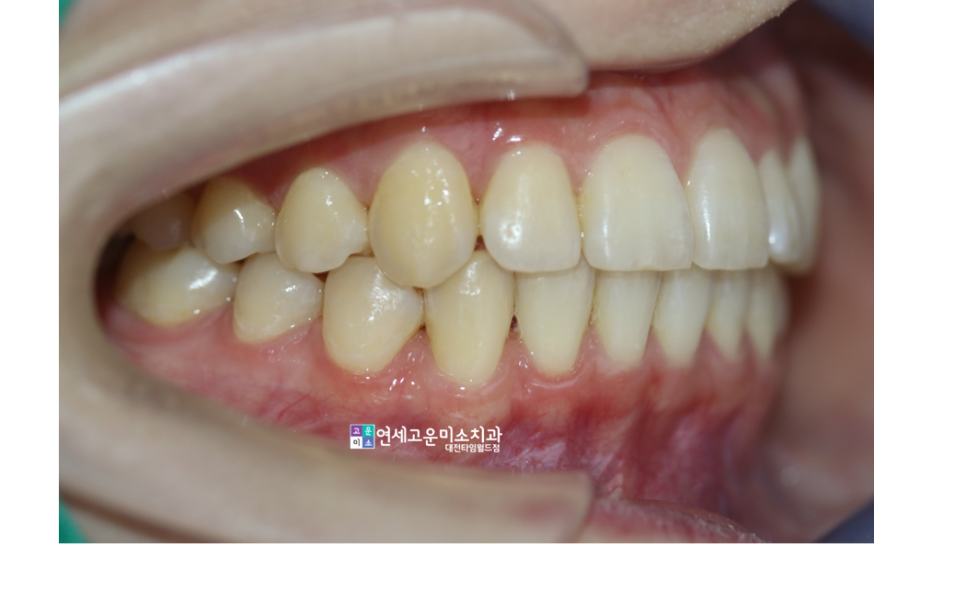

치료 후 옆모습입니다

긴밀한 교합이 형성됐습니다.

치아의 뿌리 부분의 평행도도

상당히 좋아 보입니다.

윗니가 아랫니 안으로 들어가면

불필요한 힘을 많이 받게 되면서

외상성교합으로 이어집니다.

이러면 치아를 오랫동안 사용하기가

힘들어질 수 있다고 알려졌습니다.

그렇기 때문에 심미적 개선을 넘어

장기적으로 치아를 오래 사용하도록

만들어주는 교정이 필요합니다.